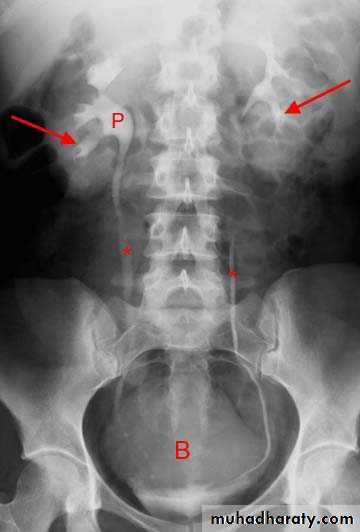

Interpretation of IVU films (what to look for?):

The kidneys:Check their position (left kidney is usually higher).

Identify the whole of both renal outlines, look for any indentations or bulges:

2.Calyces:

-should be evenly distributed -symmetrical.-Cup shaped (normal shape) -Club shaped (when dilated)

3. Renal pelvis and ureter:

-The normal renal pelvis and pelvi-ureteric junction are funnel shaped.-Ureters are seen only in part of their length on any one film due to obliteration by peristalsis.

4. Bladder

The bladder is a centrally located structure.

Other than that, any filling defect, wall irregularity or diverticula must be carefully looked for.